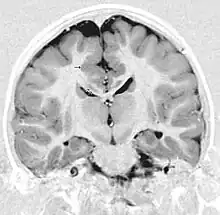

Detection of heterotopia generally occurs when a patient receives brain imaging—usually an MRI or CT scan—to diagnose seizures that are resistant to medication. Correct diagnosis requires a high degree of radiological skill, due to the heterotopia's resemblance to other masses in the brain.